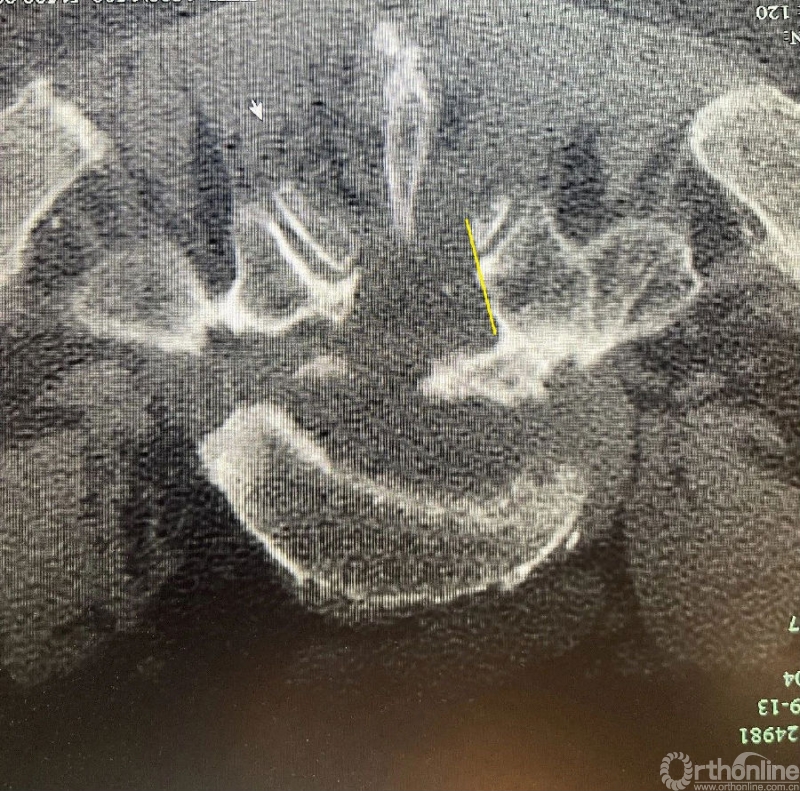

颈椎ULBD单侧入路双侧减压减压的难点还是在于识别棘突与椎板的移行部位及对侧结构的显露。

0度镜子绝对是颈椎UBE的最好用的镜子,但是30度的镜子对侧中线结构的显露及对侧结构的显露具有更广角的视野。在进行同侧减压之前,中线结构的显露是关键。

以C6/7节段病例为例,中线结构的区域解剖如下: